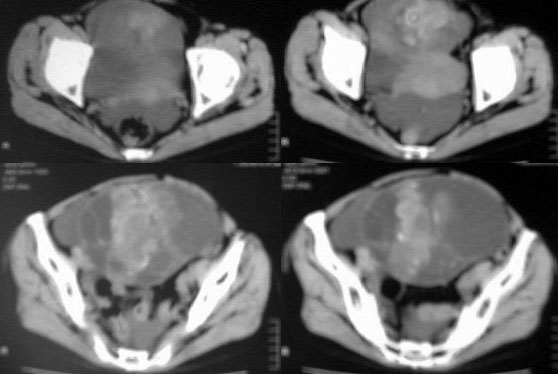

患者女性,45岁,因下腹疼痛,包块就诊,月经不太规则,其他未能提供有价值病史,请讨论

对不起各位,第一次试传,经验不足,补充一下资料,患者女性,45岁,因下腹疼痛,包块就诊,月经不太规则,其他未能提供有价值病史

卵巢囊腺癌伴腹膜转移可能性最大。

虽然没见到明显脂肪影,但是可见到明显钙化影,不排除恶性畸胎瘤的可能。

1.卵巢囊性畸胎瘤,2. 卵巢囊腺癌,道格拉斯腔积液。

ct图像有点不连续,且大部画面模糊,有增强吗?就此而论我看向源于卵巢的,首先考虑囊腺ca或瘤.

此患者手术病理结果已出:卵巢囊腺瘤。